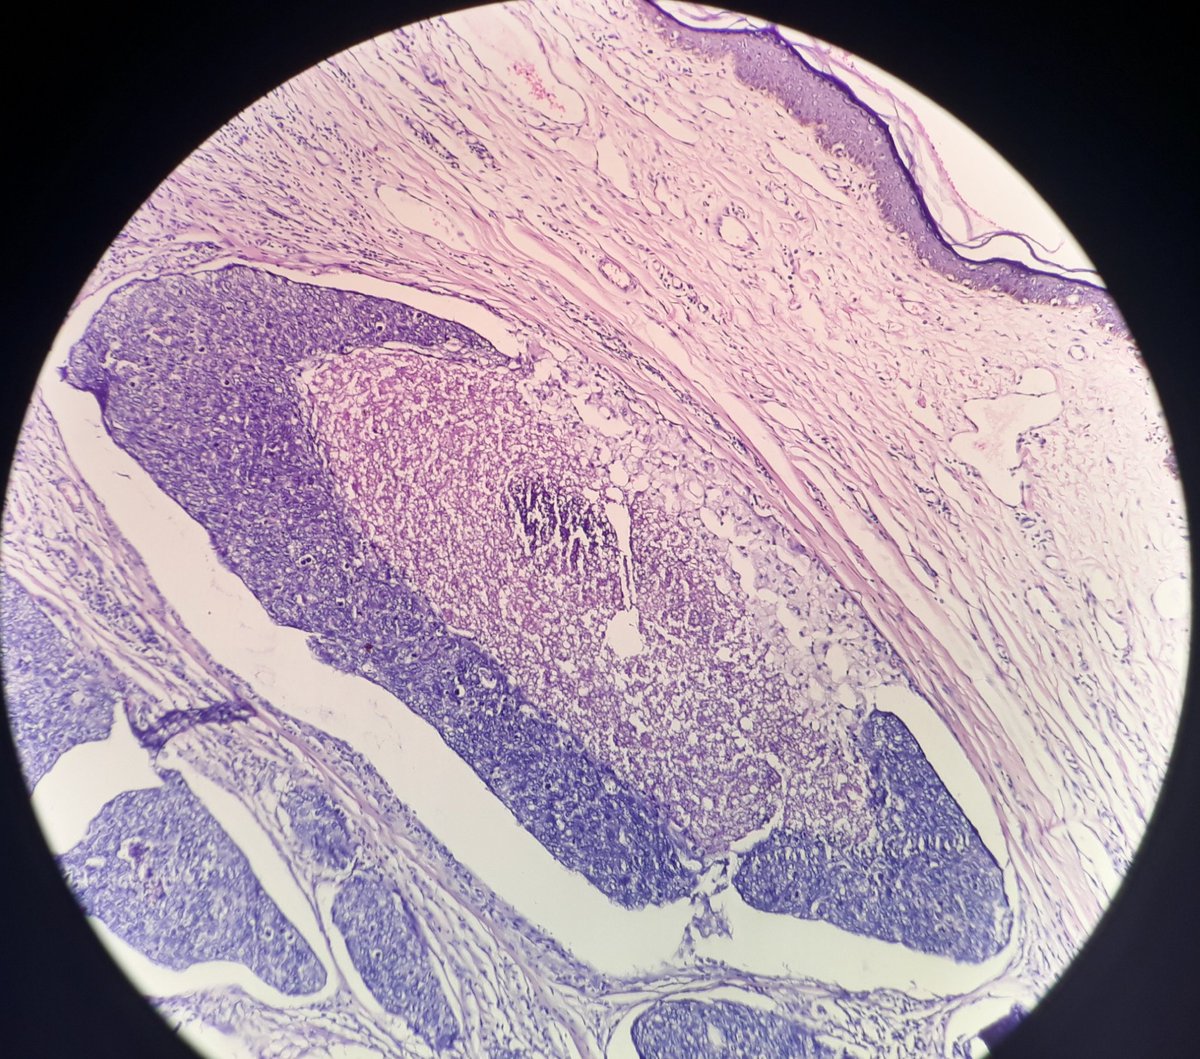

Here's a nice example of an epithelioid choroidal melanoma for your

#EyePath enjoyment pic.twitter.com/dHqb3wW4v2